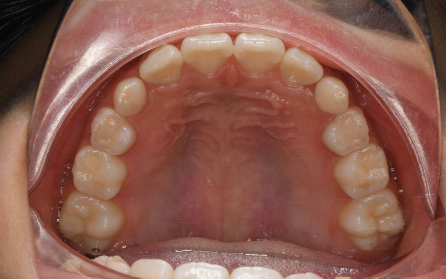

19歳 女性

主訴 「前歯のでこぼこを治したい」

診断 「両側側切歯のクロスバイトを伴う叢生症例」

上下前歯部の叢生の改善のため、歯と歯の間を0.5mm程度削ってスペースを確保しながら歯を並べました。患者さんの協力(マウスピースの使用状況等)も良好で、前歯が前方に突出することなく側切歯(2番目の歯)のクロスバイトも改善されました。前歯が突出しないように治療計画をたてないと口唇が閉じにくくなったり、口元がもっこりしてしまいます。治療期間は18か月でしたが、動的治療後は歯を安定させるために保定装置の使用が必要です(最低2年)。矯正治療では患者さんの協力が非常に重要であり(特にマウスピース矯正の場合は使用時間)、治療結果や治療期間に影響します。また、歯の移動にはワイヤー矯正、マウスピース矯正にかかわらず歯根吸収、歯肉退縮、歯髄壊死のリスクがあります。